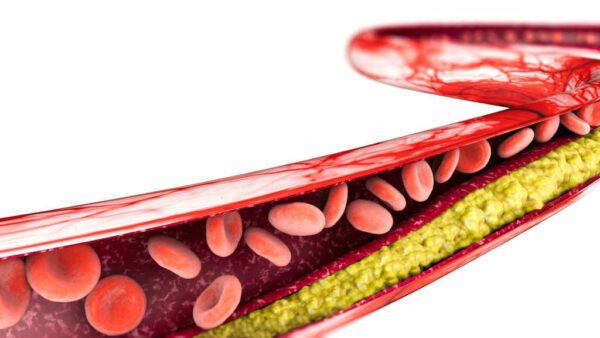

- هو تضيق أو انسداد الشرايين التاجية وعادة ما يكون السبب هو تصلب الشرايين

- إذا لم يحصل القلب على ما يكفي من الدم ، فلن يتمكن من الحصول على الأكسجين والمواد المغذية التي يحتاجها للعمل بشكل صحيح ويمكن أن يسبب هذا ذبحة صدرية أو نوبة قلبية.

اسباب مرض الشريان التاجي

تشمل عوامل خطر الاصابة بمرض الشريان التاجي ما يلي:

- ضغط الدم المرتفع.

- ارتفاع مستويات الكوليسترول في الدم.

- التدخين .

- مقاومة الأنسولين وارتفاع السكر في الدم .

- السمنة.

- هناك عدد قليل من أمراض القلب التي يمكن أن تسبب الجلطات القلبية وأحد الأسباب الأكثر شيوعًا هو تراكم اللويحات في الشرايين الذي يمنع الدم من الوصول إلى عضلة القلب.

- يمكن أن تحدث الجلطات القلبية أيضًا بسبب الجلطات الدموية أو تلف الأوعية الدموية او تشنج الأوعية الدموية.

- في حالة ارتفاع الكوليسترول الضار في الدم وتركه دون علاج ، يمكن أن يسبب العديد من المشاكل الصحية مثل النوبات القلبية أو السكتة الدماغية والاصابة بجلطات الدم.

- يؤدي ارتفاع نسبة الكوليسترول في الدم إلى تصلب الشرايين وصعوبة تدفق الدم ويمكن أن يؤدي هذا إلى مضاعفات خطيرة.